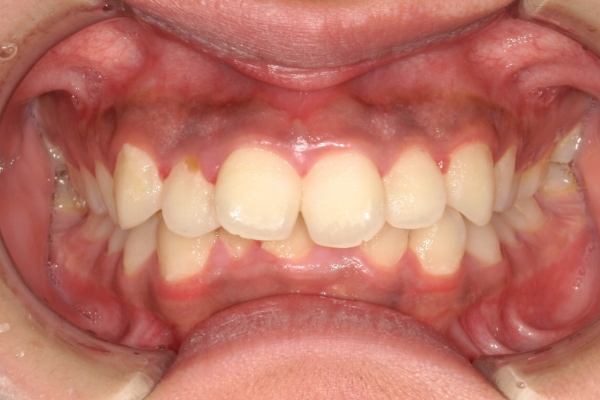

BEFORE

治療前

AFTER

治療後

上顎前歯が1 cm近く前方に出ており、叢生を改善しつつ前歯を大きく引っ込めるために上下顎小臼歯の抜歯が必要と診断しました。治療では奥歯の噛み合わせのズレも整え、治療後は前歯でも奥歯でも食べ物が噛みやすくなったと、患者さまに非常に満足していただけました。